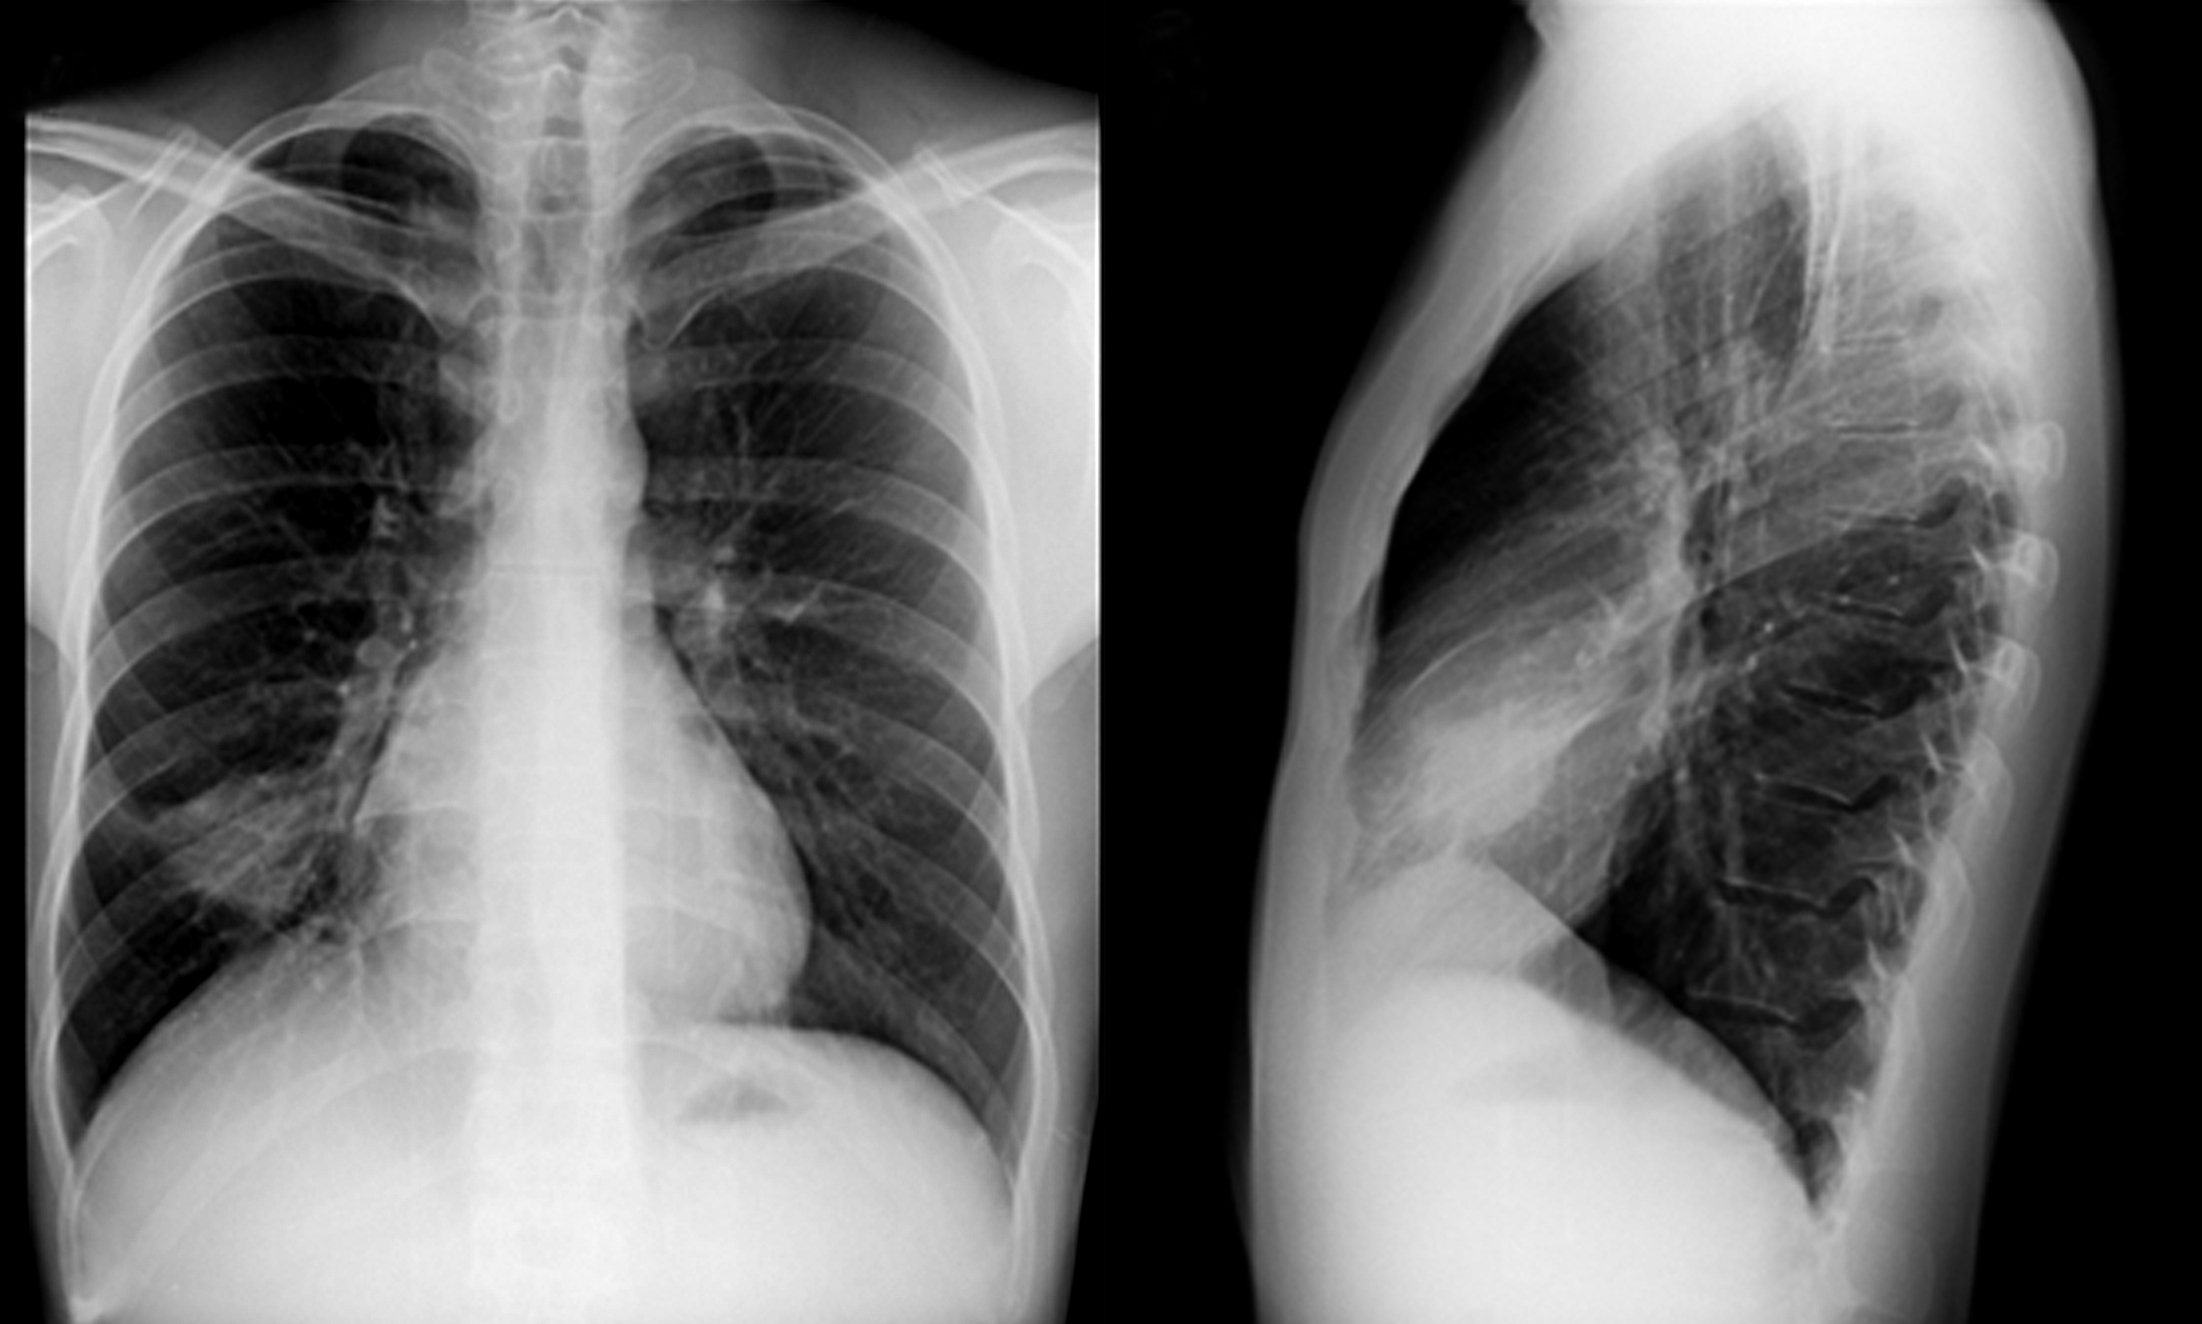

Se solicita radiografía de tórax de frente y perfil (Figura 4) en la que se observa una masa localizada en lóbulo medio, redondeada, bien delimitada, de 4 cm de diámetro mayor, sin otras alteraciones en campos pulmonares y silueta cardiomediastínica.

Figura 4

Radiografía de tórax, proyección PA (a) y perfil (b) donde se observa masa redondeada bien definida situada en el lóbulo medio.